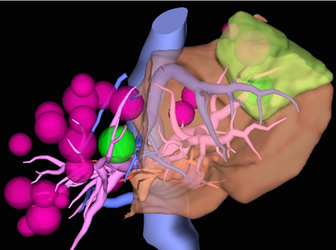

このCT画像をもとに3D構成をした画像が上図となります。腫瘍(ピンクや緑の球体で表示)は肝臓の右側(図では左側)に多く位置しておりますが、肝臓の左側(図では右側)や肝臓の深部にも腫瘍が存在していることがおわかりになると思います。このような症例では、施設によっては手術が困難とされることもあるかもしれませんが、手術の方法を工夫することで十分に取りきることが可能と我々は考えます。